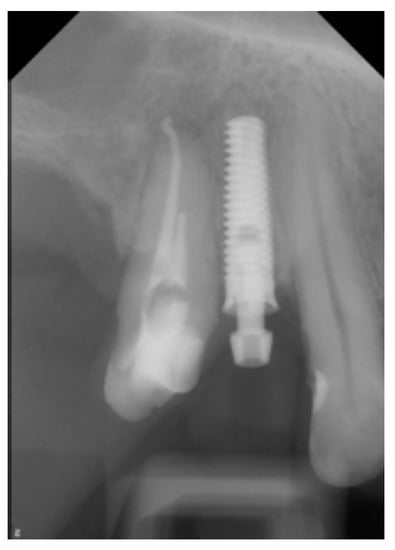

| Implant position | Tooth 14 (upper left first premolar) |

| Implant type | Tissue-Level (Matrix, TRI Swiss Implants) |

| Implant diameter platform | 3.7 mm |

| Implant diameter enossal | 3.3 mm |

| Implant length | 11.5 mm |